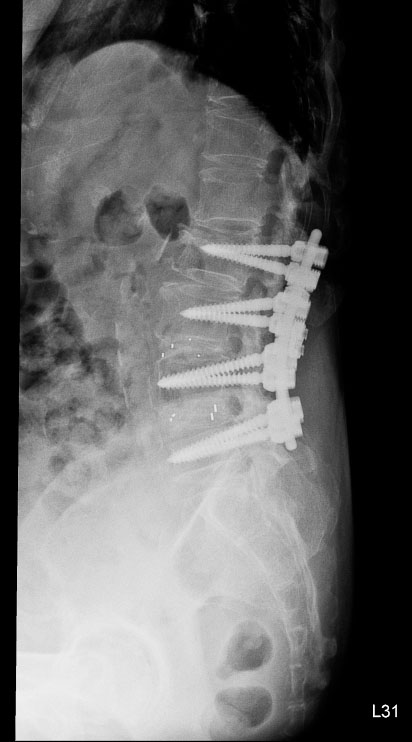

高齡翻修手術:

截釘技術降低風險

脊椎手術中最具挑戰性的情況之一,是需要再次手術的「翻修病例」。林英超主任說明,需要「翻修」的病人通常曾接受過脊椎固定手術,患部組織已形成疤痕與沾黏,再次手術時神經受傷風險提高。此外,翻修病人多屬高齡,往往伴隨骨質疏鬆或慢性疾病。

八十五歲的林女士在十多年前與七、八年前曾分別接受兩次腰椎手術,近來卻出現劇烈腰痛,翻身時疼痛指數高達八分,甚至難以入睡。影像檢查發現,她的腰椎第一與第二節出現嚴重狹窄,需要再次手術。

神經醫學中心團隊採用「截釘翻修技術」,處理高齡與多次手術史的複雜個案。「截釘翻修技術」的概念並非完全拆除舊有植入物,而是在原有固定系統仍可利用的情況下,截短或延伸固定桿,再重新連接新的固定結構,如此可以避免大範圍拆除植體與肌肉剝離。

林女士的手術過程順利,術後十天疼痛感即明顯緩解。兩個月後,她已能每天步行半小時,生活品質大幅改善。對她而言,最大的改變是終於能夠「一覺睡到天亮」。

神經醫學中心統計顯示,近兩年共有五十多名患者接受截釘翻修手術,平均出血量比傳統延長固定手術少約一百五十毫升。對於高齡或慢性病患者而言,出血量減少意味著感染與心血管負擔也隨之降低。

術前

術後

林女士術前與術後的影像檢查結果。